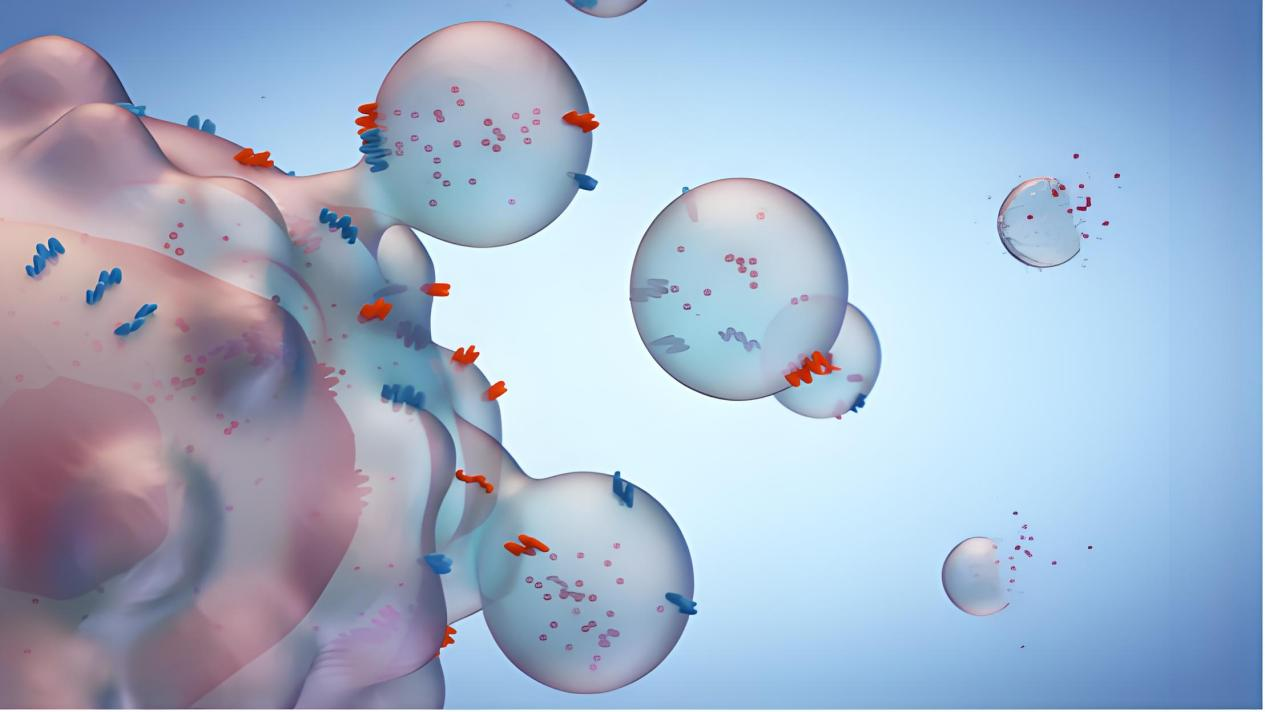

?21世紀見證著生命科學的革命性突破,以CAR-T療法為代表的免疫細胞療法在2013年被《科學》雜志評選為年度最具價值科學突破。這項被譽為繼手術、放療、化療后的"第四種腫瘤療法",正在重塑人類對抗癌癥的版圖。